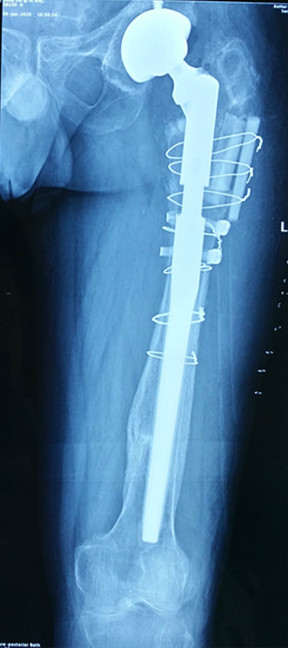

三次翻修

患者宋先生,60岁,20年前在施工时不慎受伤,导致左髋部股骨颈骨折。在当地医院接受了“左侧人工股骨头置换”手术。7年前,患者再次受伤,导致左侧人工髋关节“假体周围骨折”。接受了“左人工髋关节二次翻修术”。1年前患者出现了左侧髋部慢性疼痛,半年前疼痛加重来我院就诊,X线检查提示“左人工髋关节假体松动下沉,周围骨质大片缺损”,诊断“人工髋关节术后感染”。

经过关节外科专家组讨论后,对该患者制定出一整套治疗方案。第一步,旷置手术。先要取出患者的人工关节假体,彻底去除假体周围细菌滋生的“生物膜”并行细菌学检查,然后将含有抗生素的骨水泥制作的“占位器”放置其中。第二步,抗感染。术后根据培养结果给予敏感抗生素抗感染治疗。第三步,再次翻修。感染完全控制后,取出“占位器”,行“人工关节三次翻修手术”。